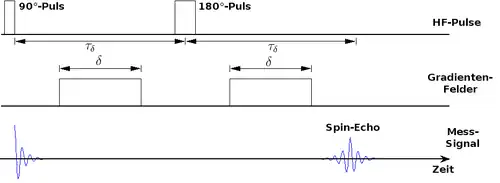

Eine diffusionsgewichtete MRT-Sequenz (siehe Schema) beginnt damit, dass der Summenvektor zunächst um 90° in die xy-Ebene gekippt wird. Die Diffusionswichtung geschieht durch ein kurzzeitig geschaltetes Gradientenfeld, das die Feldstärke des äußeren Magnetfelds in einer vorgegebenen Richtung variiert. Entlang dieser Richtung präzedieren die Kerne nicht mehr mit der gleichen Larmorfrequenz; sie geraten aus der Phase und die in der Mess-Spule induzierte Spannung verschwindet.

Anschließend kehrt man mit einem erneuten HF-Puls die Drehrichtung der Kerne um (180°-Puls) und schaltet nochmals das gleiche Gradientenfeld ein. Aufgrund der identischen Frequenzunterschiede bei umgekehrter Drehrichtung gelangen die magnetischen Momente nun wieder in Phase und es tritt erneut eine Spannung auf, das Spin-Echo. Dies ist allerdings schwächer als das Signal zu Beginn der Sequenz, da ein Teil der Kerne nicht wieder in Phase gerät – das sind insbesondere diejenigen, die sich während der Messung in Richtung des Gradientenfelds bewegt haben. Eine Diffusionsbewegung in dieser Richtung äußert sich also in einer Abschwächung des Signals.

Wie oben beschrieben schwächen auch Spin-Spin-Wechselwirkungen das Spin-Echo ab; die Auswirkungen von Feldinhomogenitäten werden dagegen durch die Mess-Sequenz eliminiert. Um den Einfluss der Diffusionsbewegung abschätzen zu können, ist daher zum Vergleich eine zweite Aufnahme notwendig, in der kein Gradient geschaltet wird.